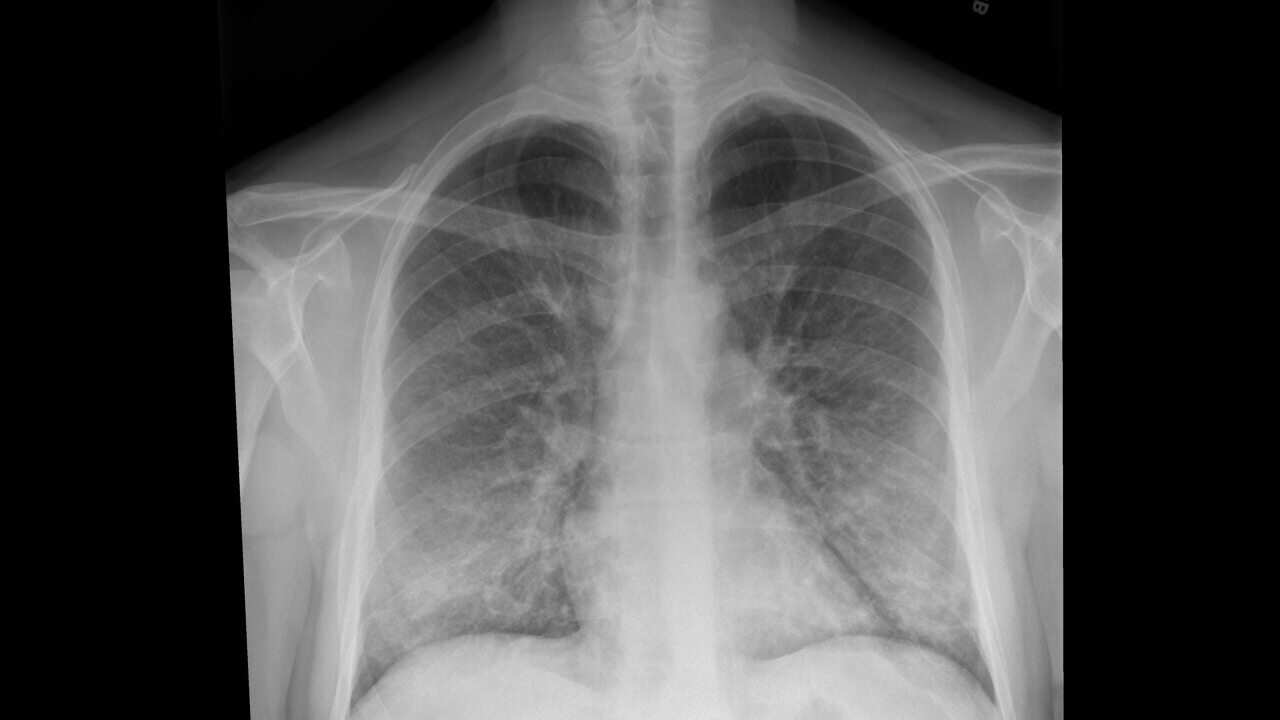

An X-ray of a patient with a vaping habit, showing lung damage densities typically associated with some pneumonias Source: The New York Times